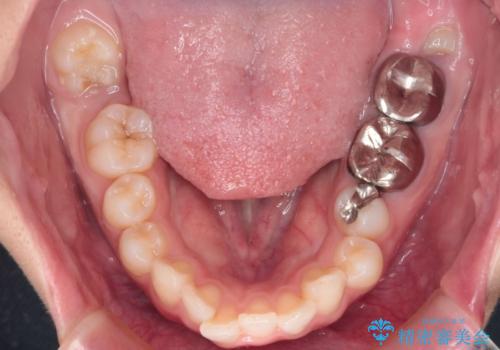

- 前歯が出ていることを主訴に来院された患者様です。

抜歯を希望されなかっため、臼歯部の遠心移動やIPRを行い配列を行っています。

抜歯をしていない矯正となるため、口元に大きな変化は認められません。